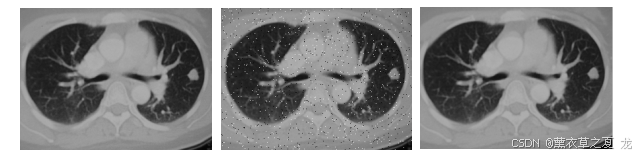

实验1 在原始图像增加方差0.02的椒盐噪声后。使用标准中值滤波方法进行处理。

结果如图1和表1所示。图1(a)为原始灰度图像;图1(b)为加了方差0.02的椒盐噪声后的图像;图1(c)为用中值滤波处理图1(b)得到的图像。

图1(a)原始图像 图2(b)加椒盐噪声 图3(c)滤波后图像

结合比较图1和图2,表1和表2可得:实验2中添加了方差为0.25的椒盐噪声模糊的图像的大部分细节,但中值滤波都取得了不错的去噪效果,基本上去除了噪声的影响。对比采用3X3和7X7窗口的中值滤波效果,同时结合对应的RPSN值,可以看出采用7X7窗口的中值滤波,边缘细节有不少损失,图像比采用3X3窗口的方法更加模糊。可得结论为:中值滤波对于低密度的噪声信号有很好的去噪效果,但对于高密度的噪声去噪效果不是非常好。